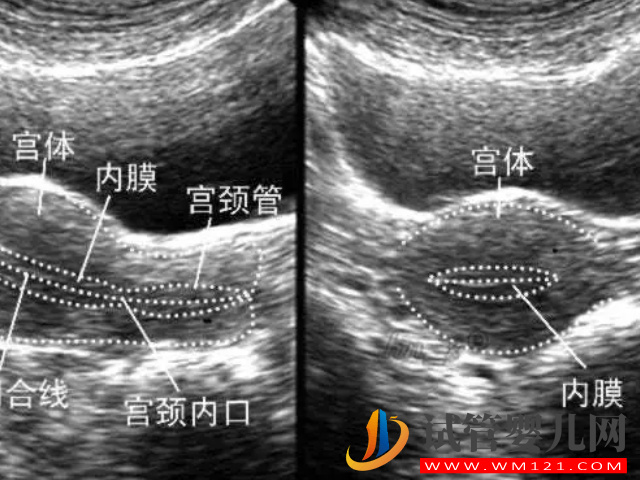

子宫内膜的厚度是会随着月经周期发生变化的,所以在每个阶段检查的参考值可能是不一样的,而在临床上面可以通过临床变现和阴超检测排判断自己是否是子宫内膜过薄。

2、阴超检测

其实现目前准确定的判断你是否有子宫内膜薄的情况,其最主要的就是通过超声检查,如果说在检查下发现自己内膜的厚度并非没有达到合适的范围,低于就是过薄,高于就是过厚,都是不利于身心健康的。